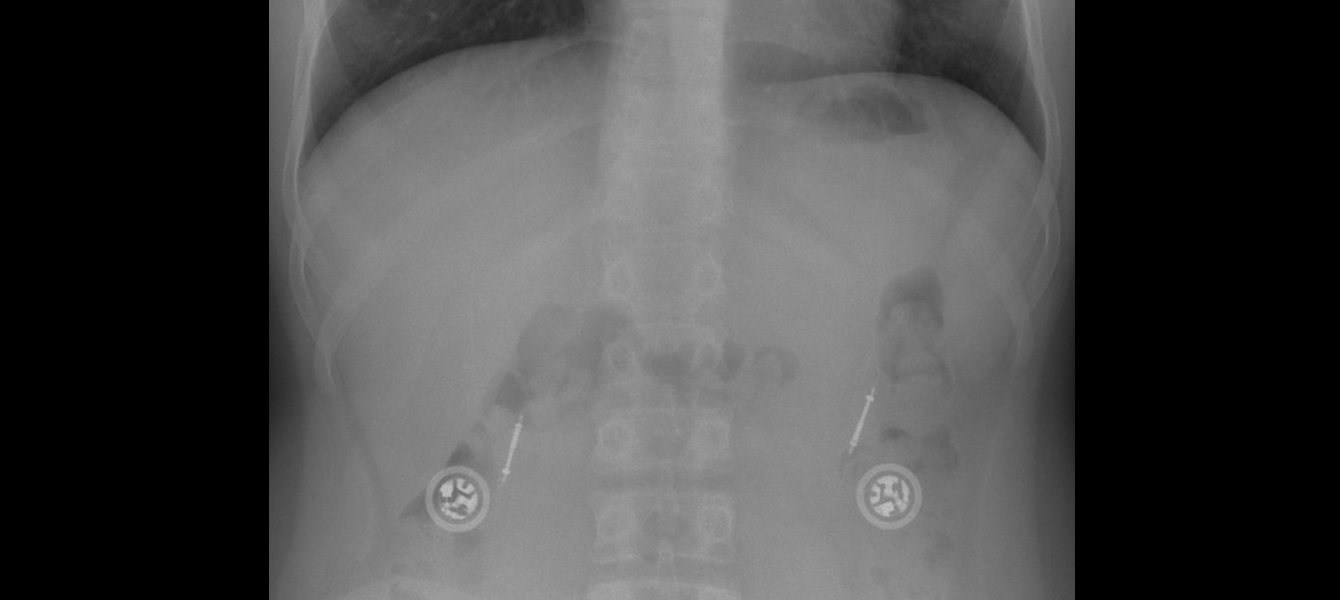

Bild: © Hellerhoff / CC BY-SA 4.0